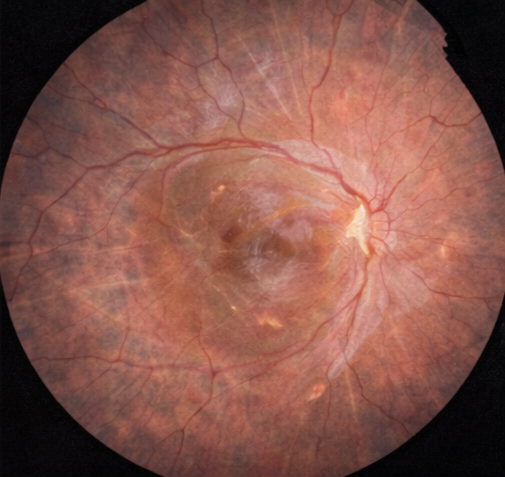

Dilated fundus examination of the right eye revealed a bullous retinal detachment involving the posterior pole, with clear elevation of the macula. A horseshoe-shaped retinal tear was identified in the superotemporal quadrant, with surrounding lattice degeneration. The left eye fundus examination was unremarkable.

Spectral-domain OCT of the right eye confirmed macular detachment with accumulation of subretinal fluid beneath the fovea and loss of normal foveal contour.

The outer retinal layers showed early disruption of the ellipsoid zone, suggestive of photoreceptor stress without established atrophy. OCT imaging of the left eye was normal.

B-scan ultrasonography demonstrated a mobile, undulating retinal membrane consistent with rhegmatogenous retinal detachment. No vitreous hemorrhage, choroidal detachment, or intraocular mass was identified.

Based on the clinical presentation, fundus findings, and multimodal imaging, a diagnosis of macula-off rhegmatogenous retinal detachment involving the right eye was established. The relatively short duration of macular involvement supported an urgent surgical approach to maximize the potential for visual recovery.